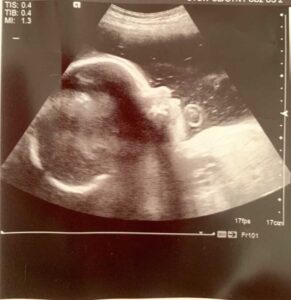

After printing out our ‘glamour shots,’ as she called them, she said she was going to go get the doctor to examine all the measurements, and left me lying there with the gel still on my stomach ‘just in case the doctor wants to take a few more measurements.’ Our second clue. She had left the screen up, which listed all the measurements she’d taken, with the Hadlock abbreviations for biparietal diameter, head circumference, abdominal circumference, and femur length, next to the average week associated with the measurements she’d taken. Like anyone—and, especially, people who’d had two clues something wasn’t quite right—we examined the screen. BPD: 40w0d. HC: 40w5d. AC: 32w1d. FL: 29w3d.

There was a 1o-week difference listed between my baby’s head size and femur length. Her head was already measuring full term at 35 weeks. Her femurs were measuring woefully behind. 6 weeks behind where they should be, and 10 weeks behind her head. Following a soft knock, the door opened, and a thin woman in scrubs walked in and introduced herself as one of the clinic’s high-risk obstetricians. The alarms in my head, which had begun going off while we were looking at the numbers on the screen, began blaring so loud I could barely focus. ‘High-risk?’ What was wrong with my baby? What did they find? Did they miss something at the 20-week ultrasound and were only just now seeing it? How could this happen? Everything had come back perfectly normal. How could something be happening now?

The doctor went on to explain what we had already seen on the screen. The baby’s head was measuring large—above the 95th percentile for her gestational age. Meanwhile, her femurs were measuring small—below the 5th percentile for her gestational age. The doctor went on to say this indicated a strong likelihood of some kind of skeletal dysplasia. Skeletal dysplasia. It doesn’t exactly have a warm, fuzzy sound. She told us there are hundreds of kinds of skeletal dysplasias, but to be honest, I don’t remember most of what she said after. I was stunned into silence. I do remember her saying third-trimester ultrasounds are only so accurate. The Hadlock numbers can’t account for all genetic variations (variations within our families), and everything else about her looked normal from what they could see.

The bones, although short, showed no signs of bowing, fracturing, with normal ossification. All those things seemed to indicate if she had some sort of dysplasia, it may be mild. Skeletal dysplasias are fairly rare, but the most commonly occurring kind is achondroplasia. She also said she thought they would probably have seen something in the 20-week ultrasound if it was achondroplasia, but she wasn’t sure. And then she told us she could get us some information on genetic testing or refer us for genetic counseling.